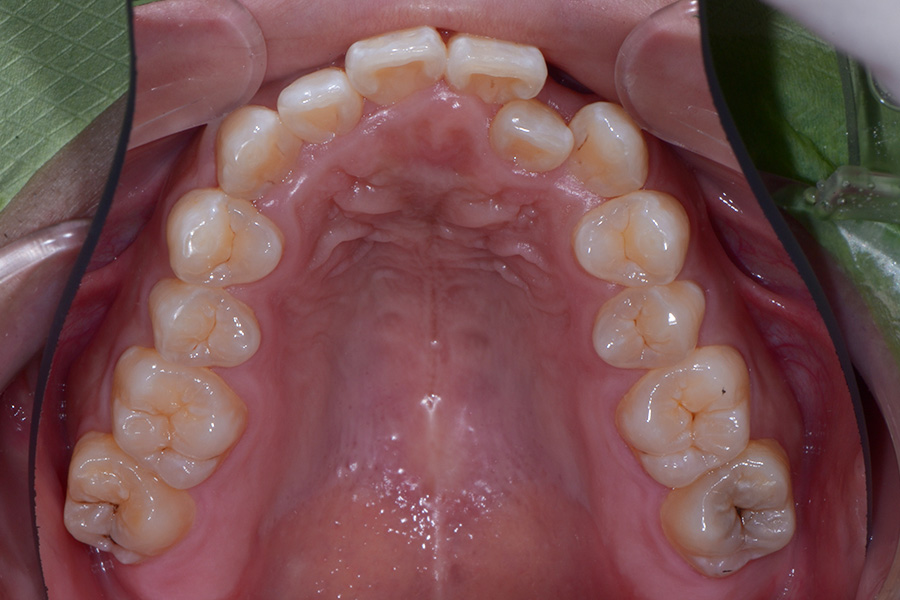

• 治療前

主訴 一本だけ隠れている歯を治したい

治療内容 上顎ラビアル矯正(表側矯正)